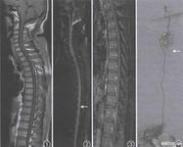

脑动静脉畸形

628健康网为您分享有关脑动静脉畸形的症状,脑动静脉畸形的治疗方法,脑动静脉畸形的预防知识,脑动静脉畸形的症状图片,脑...